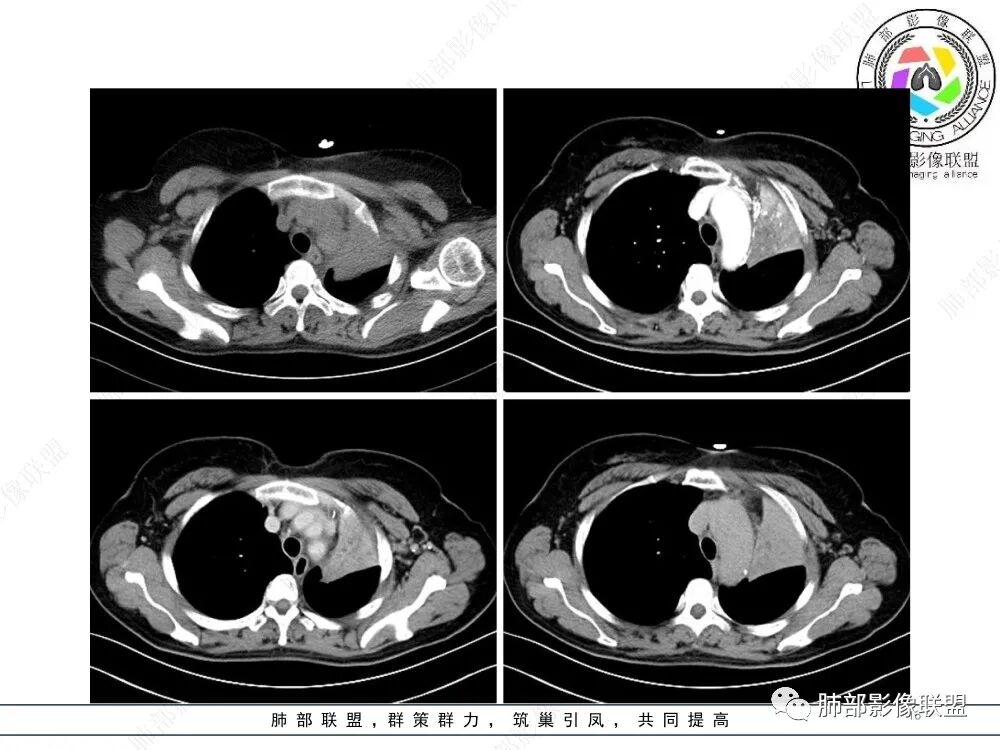

左上叶支气管堵塞,远端肺不张、实变。

病灶腔内位主,局部膨隆凸向上叶支气管,两侧壁不清,病灶明显突出于壁外。

外形近端膨隆,远端收缩。

局部肺动脉受压明显,受压处似乎有点边界不清。

远端走形自然,提示远端不张,强化最明显处应该是单纯不张肺组织。

近端病灶内强化偏低,提示有侵犯。

综上,腔内占位明确,周围侵犯明确,支持支气管腔内恶性肿瘤,并阻塞性不张。